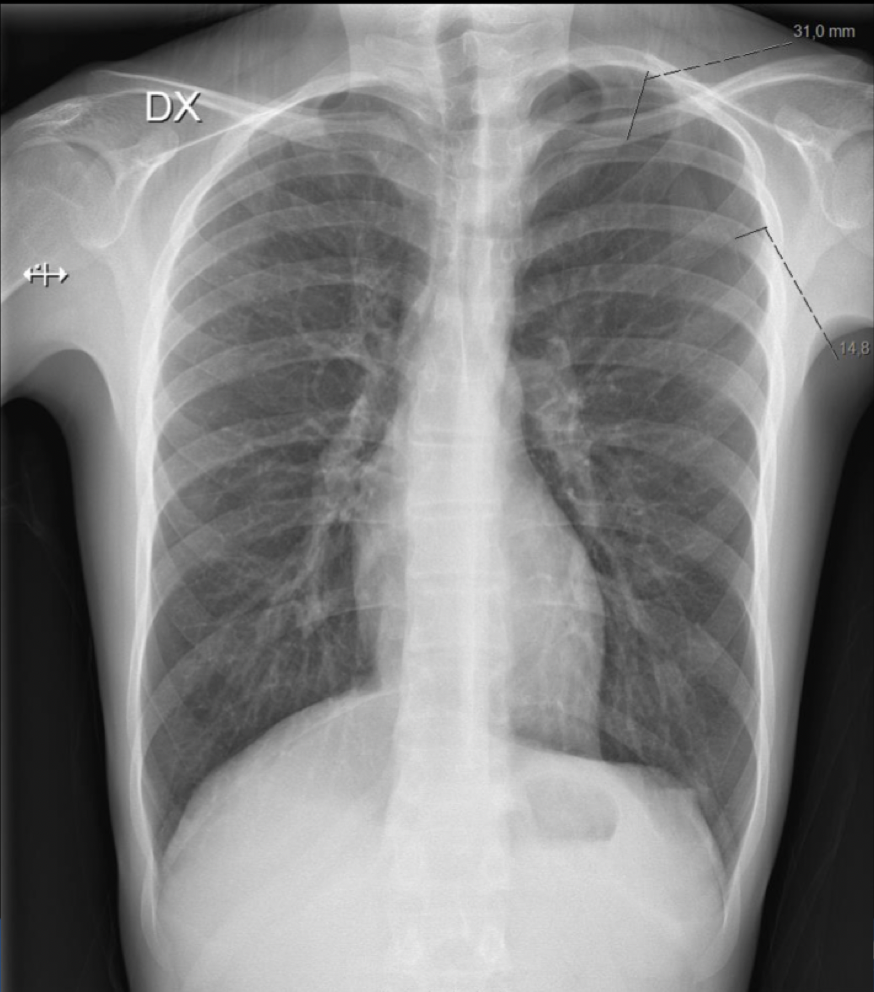

Q

Plasser anatomiske strukturer

A